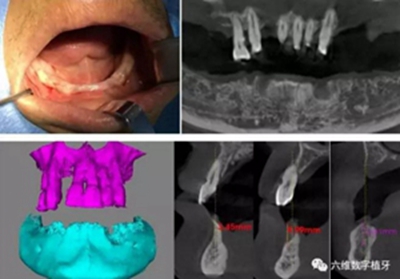

患者男,喜歡抽煙喝茶,有重度牙周病,下頜的牙齒已經(jīng)完全拔除,上頜牙齒在CT中可見,牙槽骨吸收很嚴(yán)重,牙根部分暴露,粘膜萎縮。要求:進(jìn)行下半口固定義齒即刻修復(fù)。

臨床檢查

從CT可以看出患者前牙區(qū)牙槽骨非常薄,有的地方3.5mm不到,左側(cè)4號牙位有嚴(yán)重的骨吸收,需要進(jìn)行植骨,后牙區(qū)離神經(jīng)管較近,設(shè)計種植短粗型種植體。